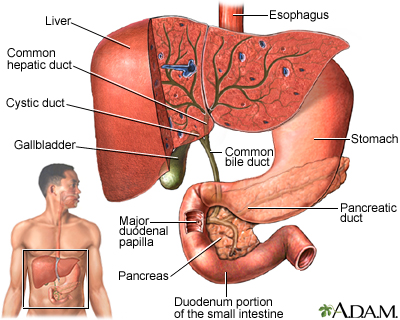

Functions of the Liver

The liver is the largest internal organ in the body. In a healthy adult, it weighs about 3 pounds. It is located below the diaphragm and occupies the entire upper right side of the abdomen.

The liver performs several vital functions, including:

Processing Healthful Nutrients.

The liver processes (metabolizes) and stores all of the nutrients the body requires, including sugars, fats, minerals (like iron and copper) and vitamins.Producing Proteins.

The liver is the body's "factory" where many important proteins, such as albumin, are made. The liver also produces essential proteins for blood clotting.Producing Bile.

The liver producesbile

, which is important for digestion. Bile is a green-colored fluid that helps the body absorb fats and fat-soluble vitamins. Bile contains bilirubin, a yellow-brown pigment produced from the breakdown of hemoglobin, the oxygen-carrying component in red blood cells.Eliminating Toxins.

An important job of the liver is to make toxic substances in the body harmless. These include substances made by the body (such as ammonia and by-products of digestion) and substances you may ingest (such as alcohol and drugs).

Disorders that block or damage the bile ducts can cause bile to back up in the liver, leading to inflammation and cirrhosis. These diseases include primary biliary cirrhosis and primary sclerosing cholangitis.